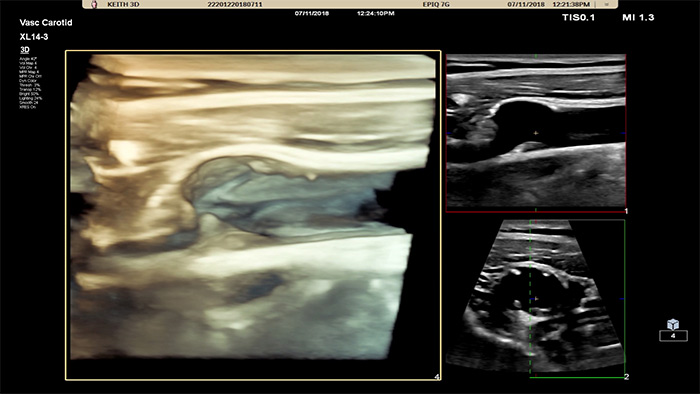

Die 3D/4D-Benutzeroberfläche bietet auch die Möglichkeit, anhand von Flussdaten ein Gefässmodell zu generieren. Die 3D-Gefässmodellierung ermöglicht die direkte Visualisierung des Flusses zur weiteren Analyse von Stenosen oder gewundenen Gefässstrukturen. Wichtigster Vorteil: Die hervorragende 3D/4D-Visualisierung der Gefässanatomie stellt eine fundierte Gesprächsgrundlage für die Entscheidungsfindung dar und optimiert die Beratung von Patienten durch besseres Verständnis ihrer Erkrankung.